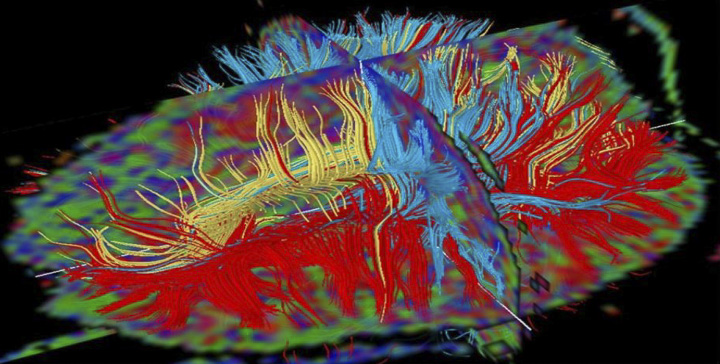

Image Processing and Analysis Core (iPAC)

Image Processing and Analysis Core (iPAC)

The vision of the Imaging Processing and Analysis Core (iPAC) is to develop novel and existing imaging biomarkers to ameliorate disease conditions. iPAC provides image processing/analysis tools and services to help scientists and clinicians develop imaging biomarkers using different imaging modalities with the goal of:

- Detecting/diagnosing diseases to enable early treatment intervention;

- Tracking disease progression/regression to evaluate the medical condition, and;

- Monitoring treatment effects to facilitate therapeutic mechanisms.

Some of the services provided by iPAC include:

- Study design to identify useful imaging biomarkers;

- Perform modeling and simulations of imaging data;

- Implement imaging methods/protocols;

- Perform image processing/analysis from different imaging modalities including MRI, X-ray, CT, microCT, OCT, PET, SPECT, ultrasound, microscopy, etc., and;

- Prepare manuscripts/proposals in collaboration with investigators.

Mohammed Salman Shazeeb, PhD, Director

Matthew Gounis, PhD, Co-Director